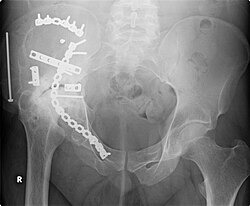

2006년 9월에 촬영된 이 사진은 2000년에 시행된 오른쪽 비구(acetabulum )의 대대적인 수리 작업 6년 후의 모습을 보여줍니다. 뼈/관절 질환인 관절염이 발병하면서 관절 손상이 더욱 뚜렷해졌습니다.